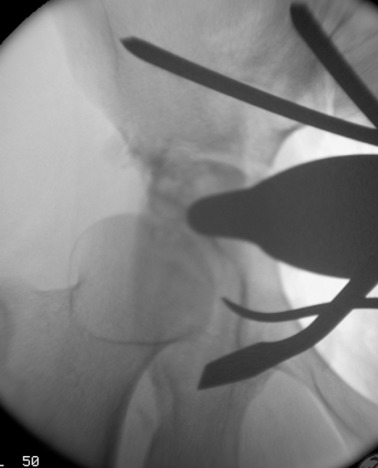

Prior to conducting the osteotomies, the greater sciatic notch, supraacetabular region, pubic rami, and quadrilateral surface were exposed, and the distances were measured as described by Shiramizu et al.15 The first osteotomy was performed on the supra-acetabular region and the iliac wing, from the pectineal line and aiming 1–2 cm distal to the medial of the anterior superior iliac spine (ASIS) (Fig. 4 ). The second osteotomy was performed on the posterior colon of the acetabulum, under fluoroscopic guidance with a 45° oblique view of the iliac. This osteotomy was from the pectineal line to the inferior ischium with an angle of 130° to the first osteotomy, leaving approximately 1 cm of bone posterior to the osteotomy line to preserve the posterior colon, as described in previously conducted anatomical studies (Fig. 5 ).15 The third osteotomy was performed on the pubic arm near to the acetabulum (Fig. 6  ;  Fig. 7 ). And the last osteotomy was performed on the distal ischium, parallel to the inferior acetabular rim (Fig. 8 ). Each stage of the operation was conducted under fluoroscopic control to ensure that the osteotome did not penetrate the joint. By twisting the osteotome under fluoroscopic guidance, it was ensured that the fragment was completely free. After completing the osteotomies, the acetabular fragment was medialized and rotated anterolaterally using a spike-tipped pusher. An anterolateral repositioning of approximately 20° was achieved under fluoroscopy. After the correction, the osteotomy was fixed with 2 or 3 3.5-mm screws (DePuy Synthes, Bettlach, Switzerland), which were inserted percutaneously from the iliac crest to the supraacetabular area, using 0.5- to 1-cm skin incisions.

Posterior colon osteotomy.

Fig. 5.